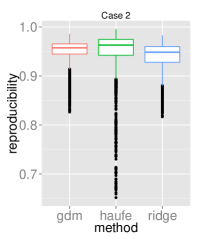

To assess the discriminative performance and reproducibility of the compared methods under varying confounding scenarios, we used the ADNI dataset. We simulated four distinct training scenarios in increasing potential for confounding effects: Case 1: AD + CN subjects, mean age balanced, Case 2: CN + AD, mean age balanced, Case 3: AD + CN, oldest ADs, youngest CNs, Case 4: CN + AD, oldest ADs, youngest CNs.

All models had their respective parameters () cross-validated in an inner fold before performing out-of-sample prediction on a left out test set consisting of equal numbers of AD and CN subjects with balanced mean age. Furthermore, the inner product of training model parameters was compared between folds to assess the reproducibility of models. Training and testing folds were shuffled 100 times to yield a distribution.

The prediction accuracies and the model reproducibility for the above cases are shown in figure 2. The results demonstrate that while GDM is not a purely discriminative model, its predictions outperformed ridge regression in all four cases. Regarding reproducibility, the Haufe et al. (2014) procedure yielded the most stable models since it yields a purely generative model. However, GDM was more reproducible than ridge regression.